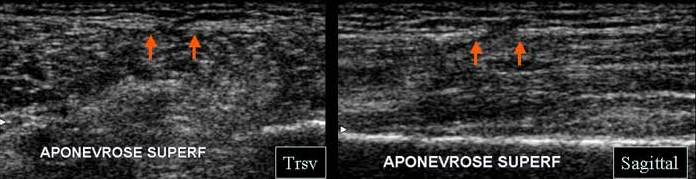

Daca in traumatismele extrinseci prin soc direct problema este in functie de sediul leziunii si nu de stadiul lezional. Este deci esentiala repérarea aonevrosei peri-musculare superficiale inaintea determarii sediului exact a lezionilor

- Sediul lezional extra-muscular, cu simpla infiltrare hematica a tesutului celulo-adipos sub-cutanat sau o veritabila decolaret, cu colectie sub-cutanata realizand un epansament de tip Morel I .

O complicatie direct legata de ruptura aponevrozei peri musculare si usor de

diagnosticat ecografic este hernia musculara

Ruptura aponevrozei superficiale